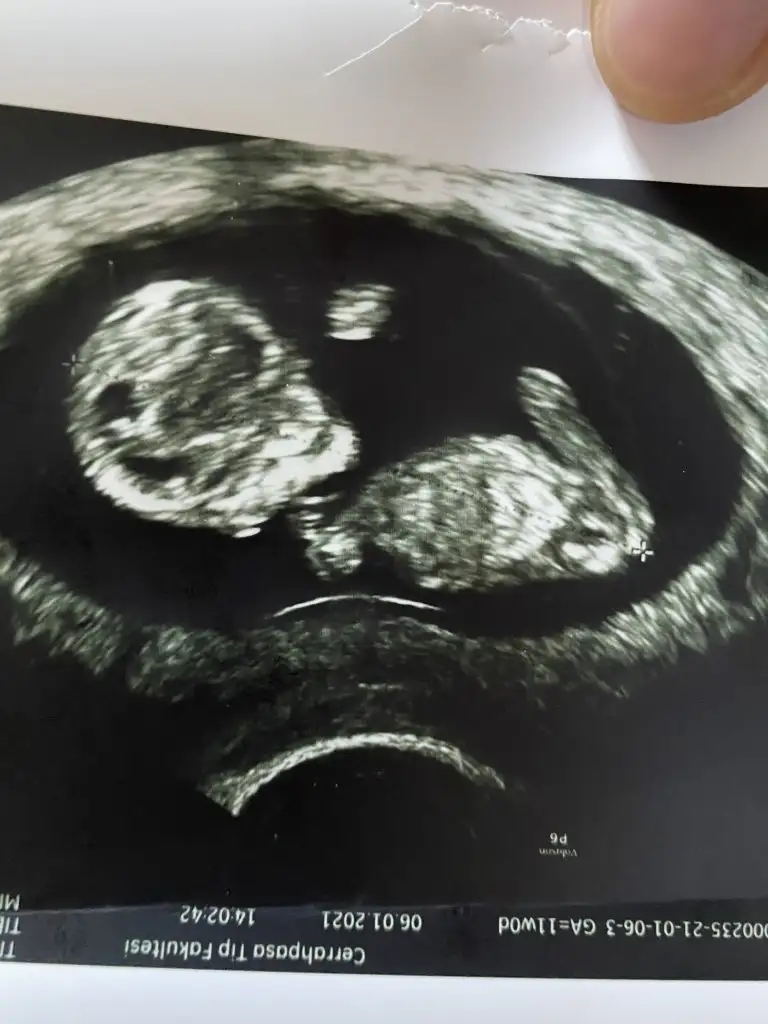

Sana yazacaktım msjı bulamadım benim yorumum bebek erkek nub teorisinde çıkıntı yukardaArkadaşlar 12. Haftada detaylı ultrasonda doktorum erkek dedi genitalin resminide çekti 14. Haftamdayım başka bir doktor kemik yapısına göre kız dedi tecrübeli arkadaşlar bakabilir mişne olsa bizim ama merak resimler 12 ve 14 hafta resimleri

Bu görüntüye göre kesin kız bebek dedi kardeşim. Ben anlamıyorum ama kızkardeşim bu işin erbabıBanada cinsiyet tahmininde bulunabilir misininz Eki Görüntüle 2781088

Bu görüntüye göre kesin kız bebek dedi kardeşim. Ben anlamıyorum ama kızkardeşim bu işin erbabıAma 12 haftaya kadar degişiklik gösterebiliyormuş. 12 haftadan sonra tekrar resim atarsanız tekrar bakabilir.

Kız dedi.Kız kardeşiniz bizim bebişe de yorum yapa bilirmi?